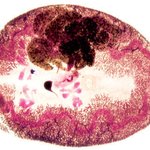

기생충!!!!!

(29)

하하네가족

|

11.05.02 11:45